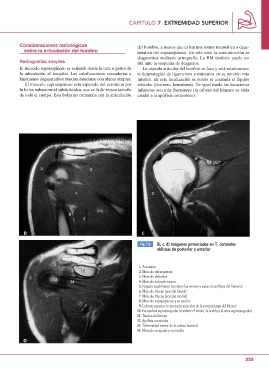

12 Fig. 7.9 (b, c, d) Imágenes potenciadas en T1 coronales

3 13 14 oblicuas de posterior a anterior

D 1. Acromion

2. Músculo infraespinoso

3. Músculo deltoides

4. Músculo redondo menor

5. Espacio cuadrilátero (contiene los nervios y vasos circunflejos del húmero)

6. Músculo tríceps (porción lateral)

7. Músculo tríceps (porción medial)

8. Músculo supraespinoso y su tendón

9. Labrum superior (e inserción muscular de la porción larga del bíceps)

10. Escotadura supraescapular (contiene el nervio, la arteria y la vena supraescapular)

11. Tendón del bíceps

12. Apófisis coracoides

13. Tuberosidad menor de la cabeza humeral

14. Músculo escapular y su tendón